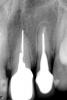

zybnaya feya Опубликовано 5 июня, 2010 Поделиться Опубликовано 5 июня, 2010 где трещина, показать можете?http://s39.radikal.ru/i085/1006/ef/7b070a653020.jpgкрасная стрелка- 99%, фиолетовая под вопросм,возможно латераль,но не особо похожа Ссылка на комментарий

leila1 Опубликовано 7 июня, 2010 Автор Поделиться Опубликовано 7 июня, 2010 Добрый день! Взяла снимок из клиники. Со штифтом мне отказались делать, сказали, что он входит всего на 2 мм и не держится. И у меня какая-то "синюшность" тканей. Скажите, пожалуйста, на самом деле есть перелом корня? У меня гной так и идет, т.е у меня вариант только удалять? Или можно обойтись без этого? Ссылка на комментарий

pawa Опубликовано 7 июня, 2010 Поделиться Опубликовано 7 июня, 2010 (изменено) Я всё же склоняюсь , что перелома нет, на первом снимке я его тоже не нашёл, но прогноз всё равно крайне сомнительный.Сфотографируйте десну. Изменено 7 июня, 2010 пользователем pawa Ссылка на комментарий

Бело4ка Опубликовано 7 июня, 2010 Поделиться Опубликовано 7 июня, 2010 Добрый день! Взяла снимок из клиники. Со штифтом мне отказались делать, сказали, что он входит всего на 2 мм и не держится. И у меня какая-то "синюшность" тканей. Скажите, пожалуйста, на самом деле есть перелом корня? У меня гной так и идет, т.е у меня вариант только удалять? Или можно обойтись без этого?Перелома может и нет, но корень под вкладку распахан настолько, что больше его использовать для протезирования нельзя. Толщина каждой стенки должна составлять как минимум треть от общего диаметра. Да и то, что свищ высоко - это не гуд. Ссылка на комментарий

zybnaya feya Опубликовано 7 июня, 2010 Поделиться Опубликовано 7 июня, 2010 Скажите, пожалуйста, на самом деле есть перелом корня? У меня гной так и идет, т.е у меня вариант только удалять? Или можно обойтись без этого?На этом снимке не видно-другая проекция. !00% подтверждение перелома вам только КТ даст. Вам верно уже несколько раз повторили-удаляйте зуб. Там тонкие стенки,огромная вкладка + за ней серебряный штифт почти до верхушки засунут. Ничего толкового с этой 2 кой не получиться Ссылка на комментарий